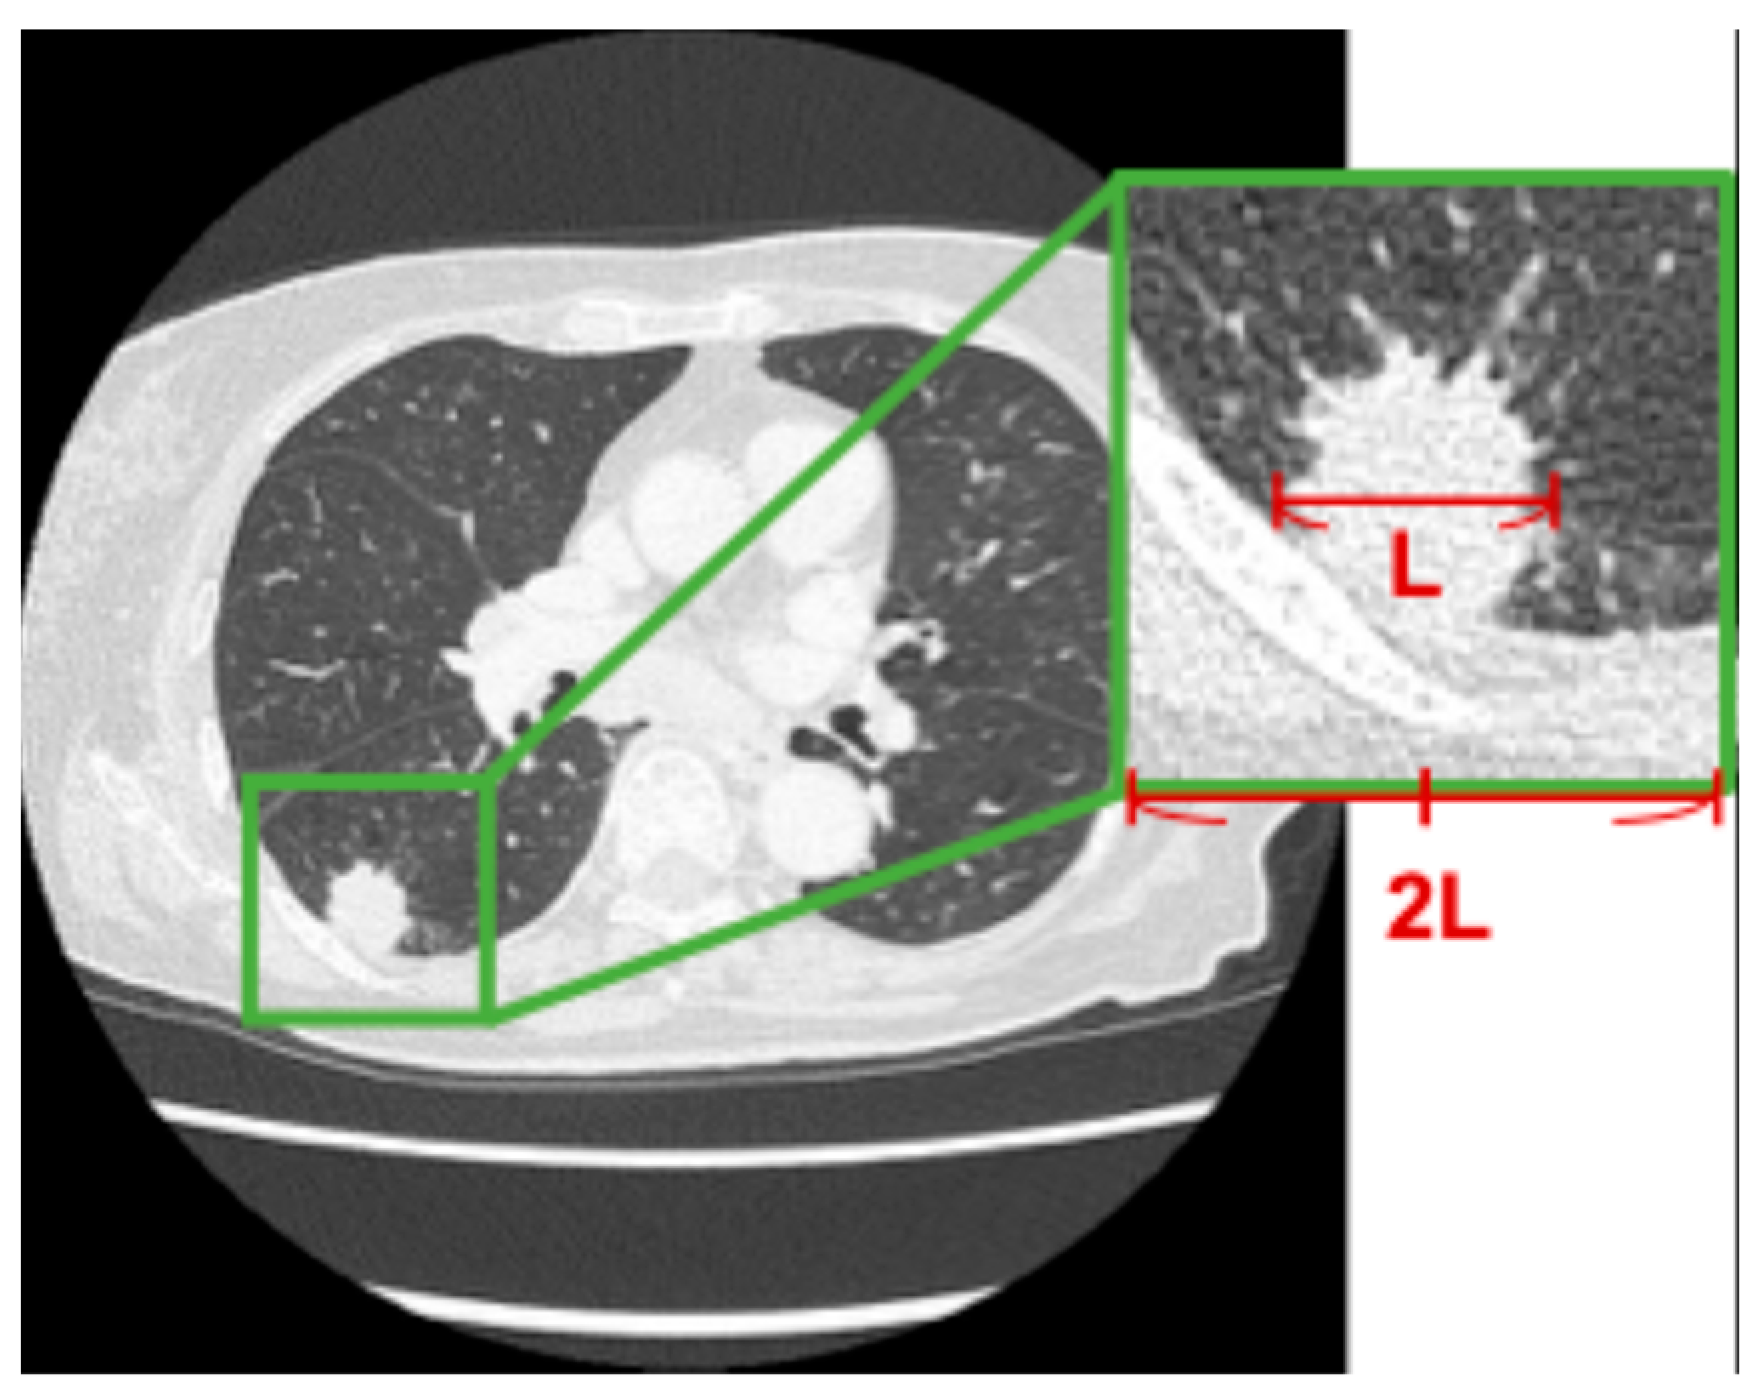

In this study, regions of interest (ROIs) around lung nodules were extracted from CT images as shown in Figure 2. In each case, an ROI centered on the tumor was extracted. The longest diameter of the lung nodule was measured, and a square ROI with a side length twice the measured diameter was defined based on the center of the nodule. This square region was cropped from the CT images.

Figure 2. Example of ROI extraction from CT images based on tumor long-axis diameter.